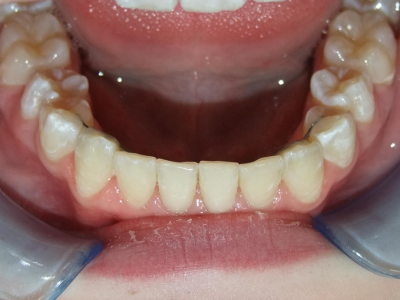

1-6 Bonded Hyrax + volledig vast onderkaak + TransForce onderkaak

7-13 Twin Block

14-28 volledig vast onder- en bovenkaak + rotator

Retentie: Wrap-Around

Leeftijd bij retentie: 12 jaar